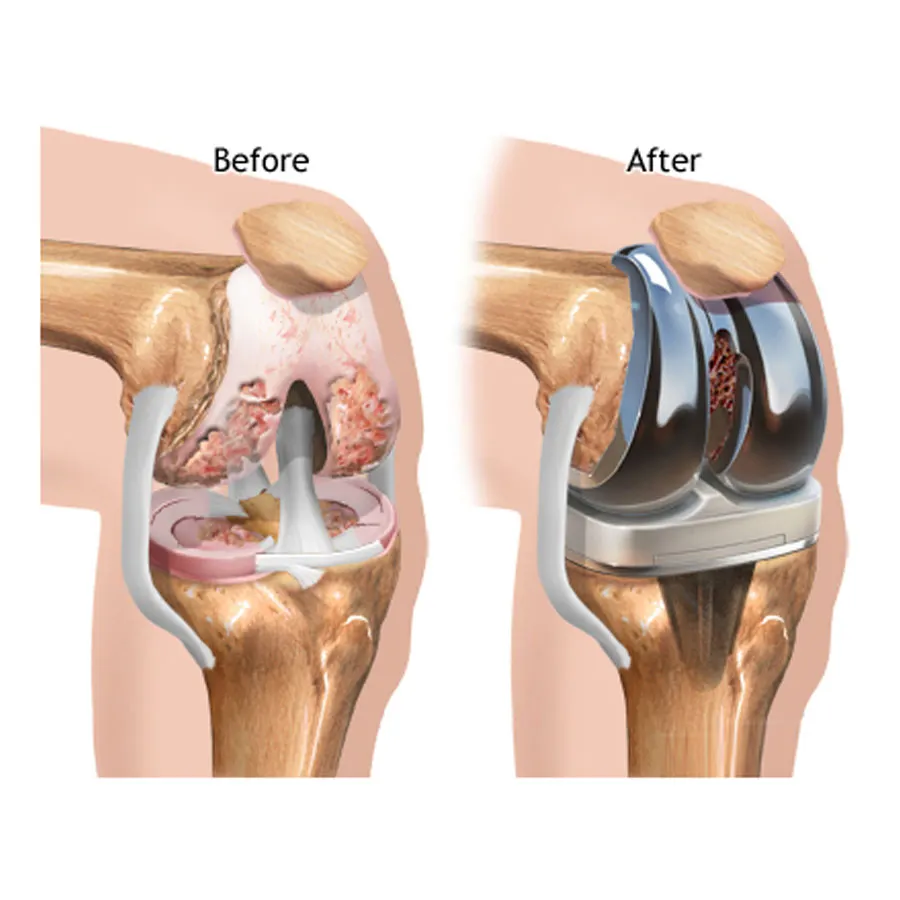

Joint Replacement

surgeries performed

Most trusted, advanced, and affordable knee, hip, elbow, limb salvage surgery in India.

Also cater to revision knee & hip replacement, post-operative care.

Dr Mujahid Saleem is an eminent Orthopaedic surgeon specialising in Joint Replacement Surgery, has exceptional Diagnostic and surgical skills operating now for over 35 years he has performed more than 20,000 surgeries using state-of-the-art techniques for optimum and functional recovery of his patients.